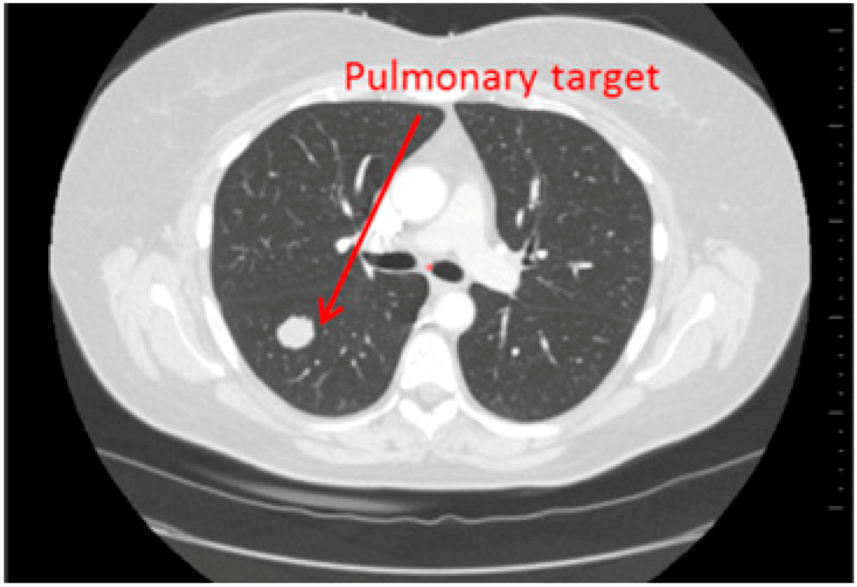

- Reading with dedicated software: Determination of RECIST response with the dedicated application for oncologic follow ups, Myrian® XL-Onco, with specific functionalities:

- 3D target matching technology to facilitate lesion localisation in the follow up study.